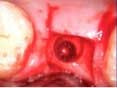

A 53-year-old female with a medical history of hypothyroidism, seasonal allergies, and asthma taking Synthroid and Singula presented to my office with pain in No. 3, failed root canal therapy, and a fracture. The tooth was deemed hopeless and extraction and implant placement was treatment planned. Under local anesthesia, tooth No. 3 was sectioned into three pieces and extracted. The sockets were debrided, filled with gel foam, and closed with chromic gut sutures. Healing was uneventful. The patient did not return for two years for follow-up. A CT scan was taken, which confirmed that approximately5 mm of bone remained below the floor of the sinus. After reviewing the options with the patient, a treatment plan of an internal sinus lift (osteotome), bone graft, platelet-rich fibrin (PRF) and simultaneous implant placement was agreed upon. Under local anesthesia, a full thickness flap with two vertical releasing incisions was performed at tooth No. 3 site. A trephine bur was used to a depth of 4 mm. An osteotome was then employed to infracture the bone core, which remained attached to the Schneiderman membrane. A bone graft consisting of DFDBA, anorganic bovine bone, and PRF was used in the osteotomy to increase the vertical bone height using sequential osteotomes. After sufficient elevation, a 7x9 tapered implant was placed on low speed to 50% of the implant depth. The remaining placement of implant was done with a hand torque on 50 ncm to allow for further expansion of the alveolar housing. A healing abutment was placed using the principles of platform switching. Healing was uneventful, and integration was successful.

Case 1: Implant and osteotome bone graft through the socket with Southern Implant